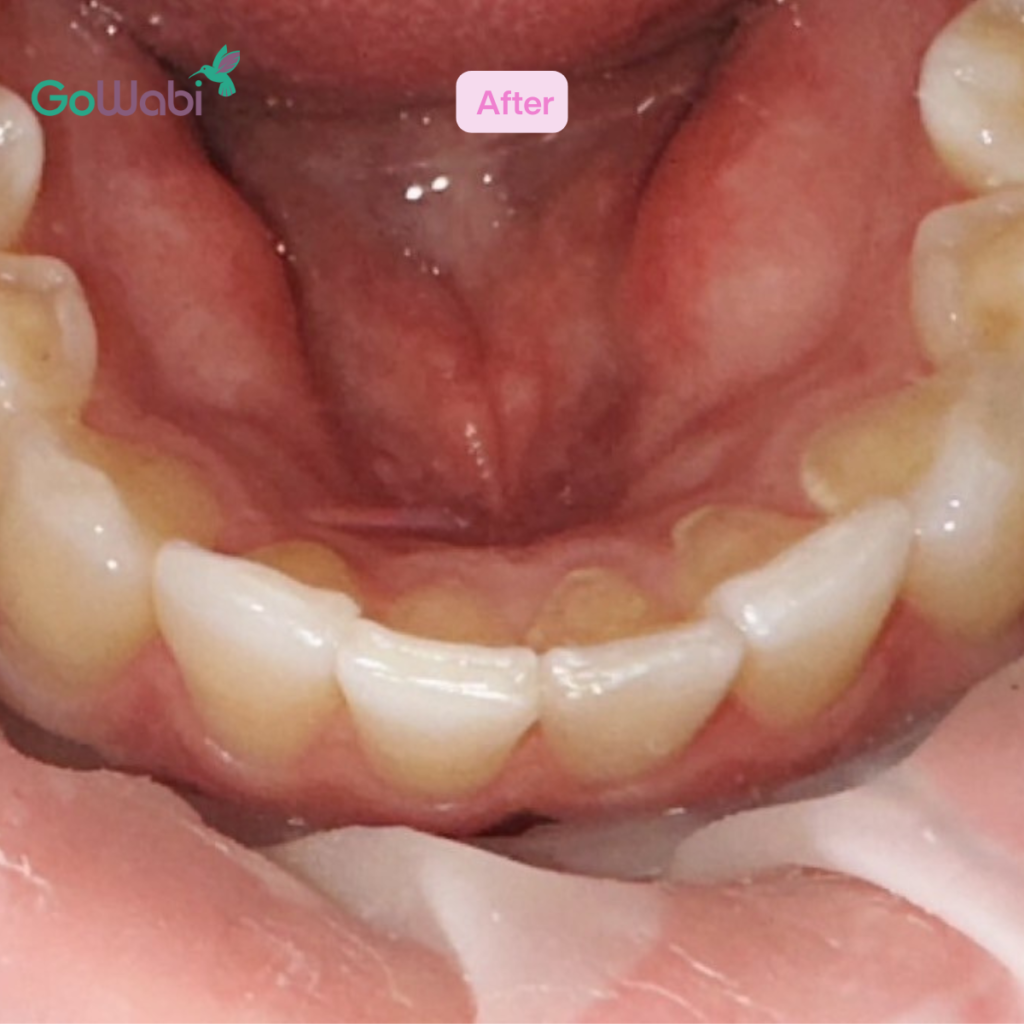

เปรียบเทียบผลลัพธ์ก่อน-หลังการจัดฟันใส Dr Clear Aligners ที่ DCA Dental Clinic

หลังทำ 1 เดือน

- ฟันเริ่มเรียงตัวสวยขึ้นอย่างเห็นได้ชัด

- มั่นใจในการยิ้มมากขึ้น

- การสบฟันดีขึ้น ไม่รู้สึกเหมือนฟันเกเหมือนก่อน